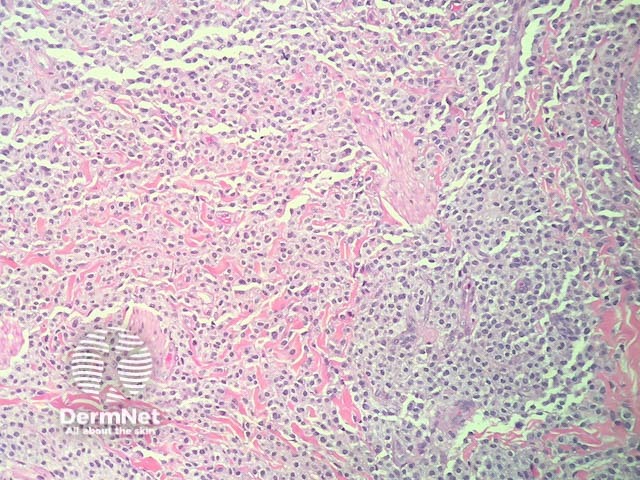

In maculopapular cutaneous mastocytosis, the histopathology shows an accumulation of mast cells in the dermis (figures 1-4). Mast cells are round or spindle shaped with abundant eosinophilic cytoplasm which contain minute granules, distinct cytoplasmic boundaries, and large pale nuclei (best seen in figures 2-4). Often there are accompanying other inflammatory cells including histiocytes, eosinophils and lymphocytes. There may be oedema of the dermis, particularly if the lesion has been traumatised.

Figure 1